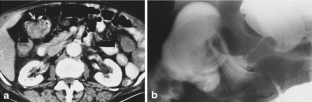

Fig. 1

Fig. 2

Fig. 3

Fig. 4

Fig. 5

Fig. 6

Fig. 7

Fig. 8

Fig. 9